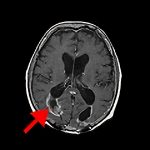

頭頂葉海綿状血管腫

No.’13_169 手術前1

No.’13_169 摘出 前

No.’13_169 摘出 後